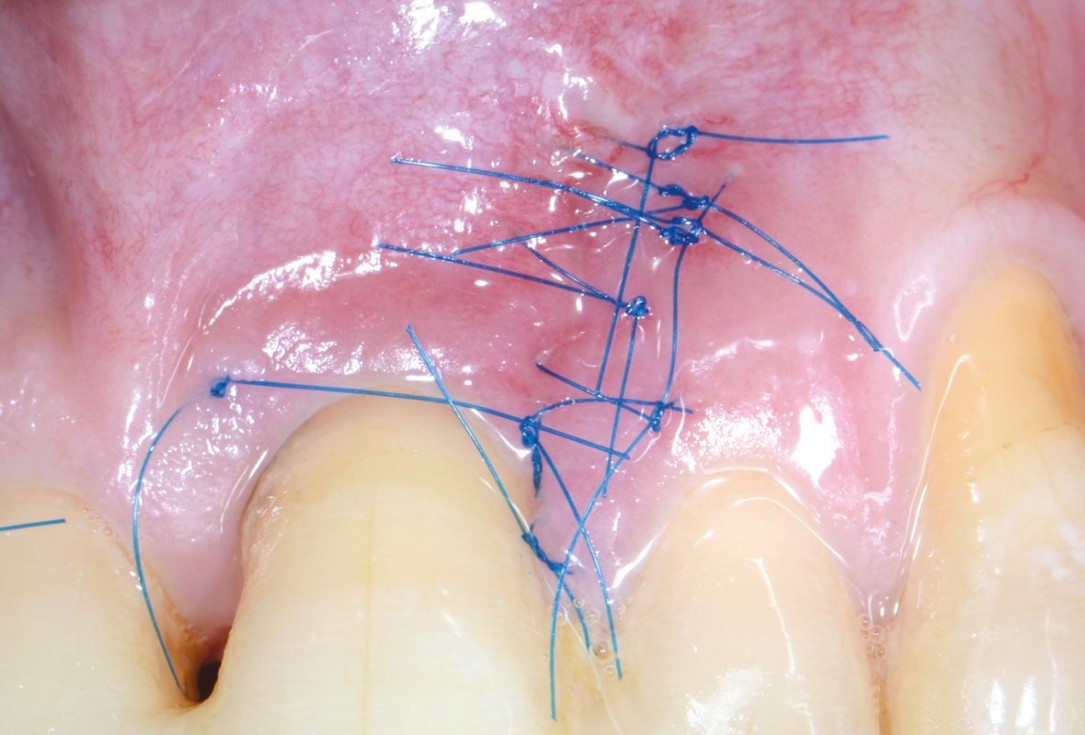

09/11 - Early wound healing at 7 days post-operativeEntire papilla preservation technique (EPP) for the regenerative treatment of a severely compromised central incisor - Dr. S. Aslan